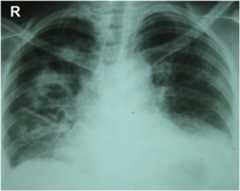

Chest radiography: Multiple nodular and cavitating lesions are visible predominately on the right side with multiple patchy infiltrates typical of granulomatosis with polyangiitis. Costophrenic angles are obliterated owing to small bi-basal pleural effusion.

Image: “Chest radiography at presentation” by Department of Pharmacology and Pharmacy, Faculty of Medicine University of Colombo, PO Box 271, Kynsey Road, Colombo 08, Sri Lanka. License:CC BY 4.0